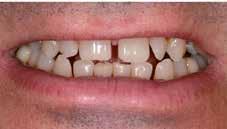

Hölgy páciensem az első konzultáció során tipikus kórtörténetet vázolt fel: Gyermekkora óta szeretett volna fogszabályozó készüléket, hiszen mindig is zavarta a class 2-es eltérésnél tipikusan jellemző nagy overjet (1-3. képek), és természetesen az ezáltal kifelé álló felső metszőfogai, részben a felső metszők protrúziója, részben pedig a disztálisan elhelyezkedő mandibula miatt. Annak ellenére, hogy több fogszabályozó szakorvosnál is járt az évek során, de mivel saggitális eltérése és az alsó metszőfogak torlódása miatt négy kisőrlőfog extrakcióját, illetve emellett sokszor állcsont műtétet is javasoltak neki, nem vágott bele a kezelésbe (4-5. képek).

A fogorvosa – nagyon helyesen – felhívta a figyelmét, hogy parodontális státusza is valószínűsíthetően romlani fog az eltérése miatt, újabb kört futott, immár 39 évesen, de még mindig premoláris fogak húzása és állcsontműtét nélkül szerette volna a fogszabályozást.

A konzultáció során arról is beszéltünk – ahogy az ilyenkor lenni szokott –, sohasem szeretett igazán mosolyogni, de a Pitts Protokolloknak köszönhetően az arc- és mosolyesztétikai céloknak megfelelően kerül megvalósításra az okklúziós korrekció. Az okklúziós kezelési célok az alábbiak voltak: a felső és alsó fogív nivellálása és tágítása, az alsó fogsor/ mandibula mezializálása, valamint a harapás megemelése által a mélyharapás rendezése.

A fogkontúrálás és az interproximális redukció alkalmazásával a mikroesztétikai részletek tökéletesítése is megtörtént (11. kép) A kezelés mindössze 16 hónapig tartott, megtörtént a rágófunkció helyreállítása, és az esztétikai végeredmény sokéves várakozás után valóban fordulópontot jelentett páciensünk életében (12-14. képek).